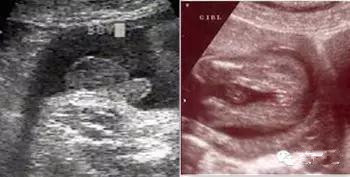

如果是男孩,B超影像可以看到*丸睾**的显影,即小茶壶样,或有点像菌状的东西;女孩子则可以看到小阴唇的显影,呈三条线状。最大的要点就是“三条线”和“凸出的东西”。

但是针对没有学过影像学的非专业人士很难看懂,更不要说看出这样的形状,不建议孕妇盲目判断。